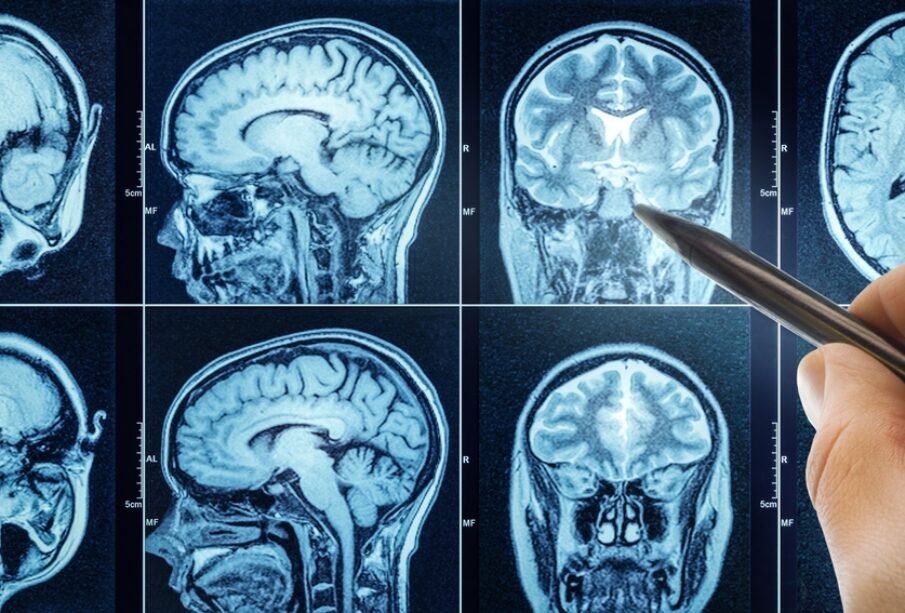

- Magnētiskās rezonanses tomogrāfija (MRT): nodrošina detalizētu smadzeņu struktūru izvērtējumu; dažkārt izmanto kontrastvielu skaidrākam attēlam.

- Datortomogrāfija (DT): tiek veikta, izmantojot rentgenstarojumu, bieži kombinācijā ar kontrastvielu.